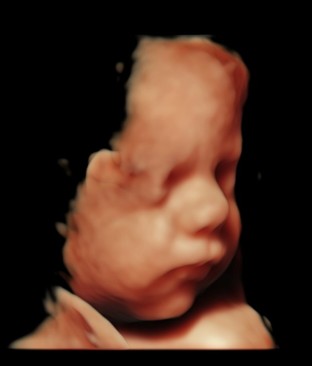

Profile of preborn baby at 10 weeks gestation

This generation has grown up under in a different world of science and technology than the Roe generation. Today’s moms see their babies on ultrasound from the earliest stages of pregnancy. They don’t have to imagine what their babies look like thanks to realistic 3D/4D scans. They know the sex of their babies just weeks into pregnancy through a simple blood test. They follow every step of their baby’s development in a pregnancy app. They understand their pregnancies in ways their grandmothers could have never imagined.

With so much information in the palms of their hands, it will be harder and harder to conceal the evidence of prenatal life from them. But can the science that confirms prenatal life be twisted?